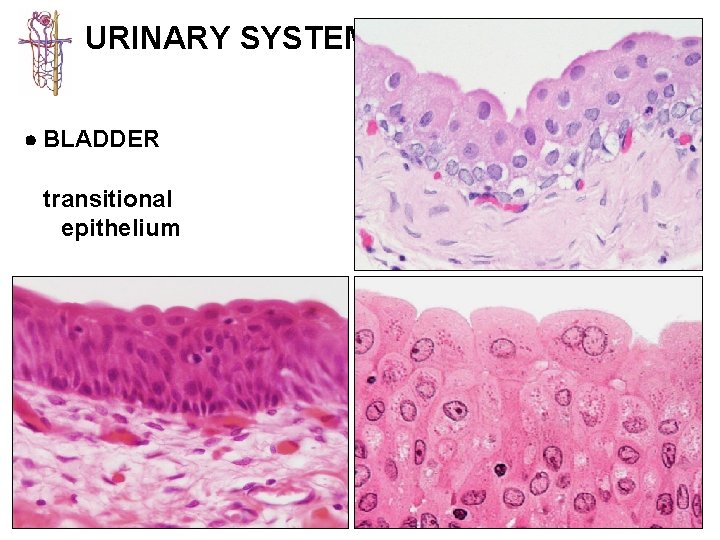

URINARY SYSTEM KIDNEY CALYCES/ URETER BLADDER URETHRA 1 - mucosa lined with transitional 2 -epithelium usually lacking submucosa 3 - muscularis best developed in ureters (2 -3 layers) and bladder (3 layers)

URINARY SYSTEM BLADDER

URINARY SYSTEM BLADDER transitional epithelium